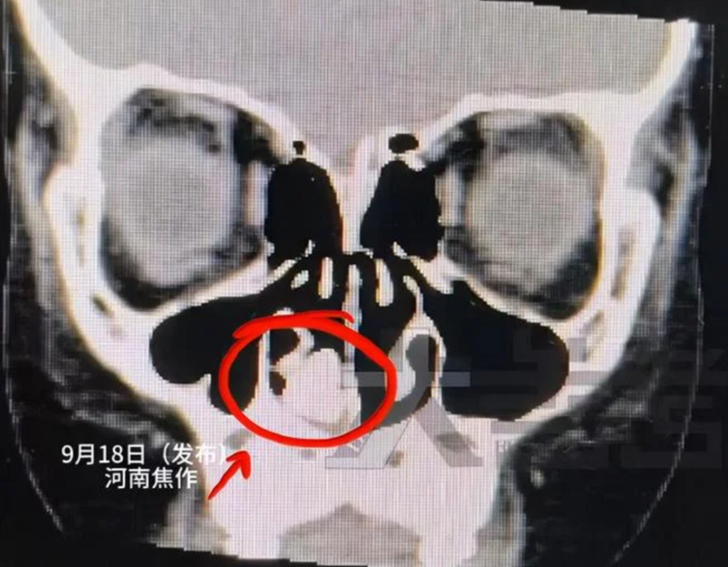

Doktorlar, çocuğun burun deliklerinin inceledikten sonra burnunda gizemli siyah bir kitle olduğunu fark ettiler. Daha sonra kafasının Bilgisayarlı Tomografi (BT) taramasıyla da bu durum doğrulandı.

Çocuğun burnuna saplanan gizemli nesne tanımlanamadı ve burun boşluğunun o kadar yukarısındaydı ki doktorlar onu çıkarmaya çalışırken ciddi hasara yol açabileceklerinden endişe ediyorlardı.

Doktorun, çocuğun burnundaki siyah yabancı cismi çıkarmadan önce üç farklı alet denediği bildirildi. Burun birkaç kat burun salgısı ve kurumuş irinle kaplıydı, bu yüzden ilk başta kimse bunun ne olduğunu anlamadı, ancak temizledikten sonra doktorlar bunun metal bir vida olduğunu fark ettiler.

Hastane sözcüsü Elephant News'e,"Nesne burun boşluğunda uzun süre takılı kaldığı için ilk başta ne olduğunu görmek imkansızdı. Dikkatli bir temizlikten sonra bunun metal bir vida olduğu keşfedildi." diye açıklama yaptı.